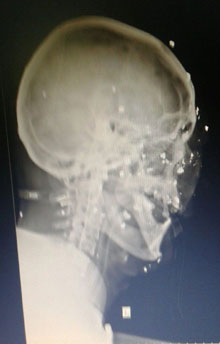

KRUŠEVLjANIN Bojan Antić (36) bio je tog 27. novembra 2016. sa prijateljem u lovu, kada je pas uočio divljač na pedesetak metara udaljenosti. Krenuo je da se približava, a poslednje što je Bojan uspeo da vidi bio je kratak let fazana iznad njegove glave. Kroz sekund-dva našao se u mraku. Drug ga je pogodio direktno u glavu! Snop dramlija iz lovačke puške, kalibra 12 milimetara, zabio mu se kroz sinuse, lobanju, u vrat, rame i stomak. Nesrećni čovek, zaljubljenik u pse i golubove, tada je poslednji put video svet oko sebe.

- Sećam se svega dok me nisu stavili u sanitet. Zatim sam danima bio u komi, a onda sam, po buđenju, shvatio da više neću videti svoju suprugu Maju (33), ćerku Milicu (13) i sina Nemanju (4) - priča za "Novosti" Antić, u Čitluku omiljen komšija, mnogima dobar drug. - Lečen sam u KC Niš, zatim na VMA. Snimanja, intervencije, vađenje milimetarskog olova iz glave, više puta ponovljene reči "zauvek slep". To sam prošao za sedam i po meseci.

- Ali to ne dozvoljavam - govori nam Antić, dok pokušava da napipa čašu vode na stolu. - Lekari su rekli da je već pravo čudo što sam ostao živ. Jer, snop iz puške ima možda tih 150 do 160 delića. Mislim da me nijedan nije promašio, bio sam na manje od 10 metara od kolege lovca.

Dramlije u Bojanovoj glavi